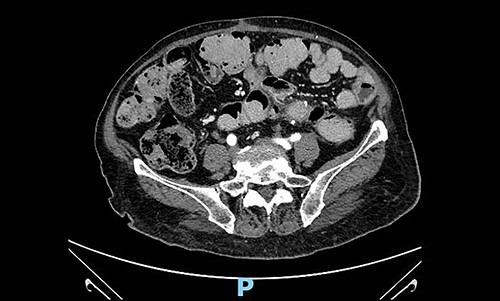

Taking into account available guidelines for soft tissues tumours and patient-related and disease-related factors, such as age, co-morbidities and histopathological characteristics, after a careful assessment of risk–benefit, clinical and radiological follow-up with abdominal-chest CT scan every four months was established by a multidisciplinary group. At the first follow-up visit and CT scan (4 months after surgery), there was no recurrent disease (Fig. 4).

Abdominal contrast-enhanced CT scan 4 months after surgery: no evidence of local recurrence.